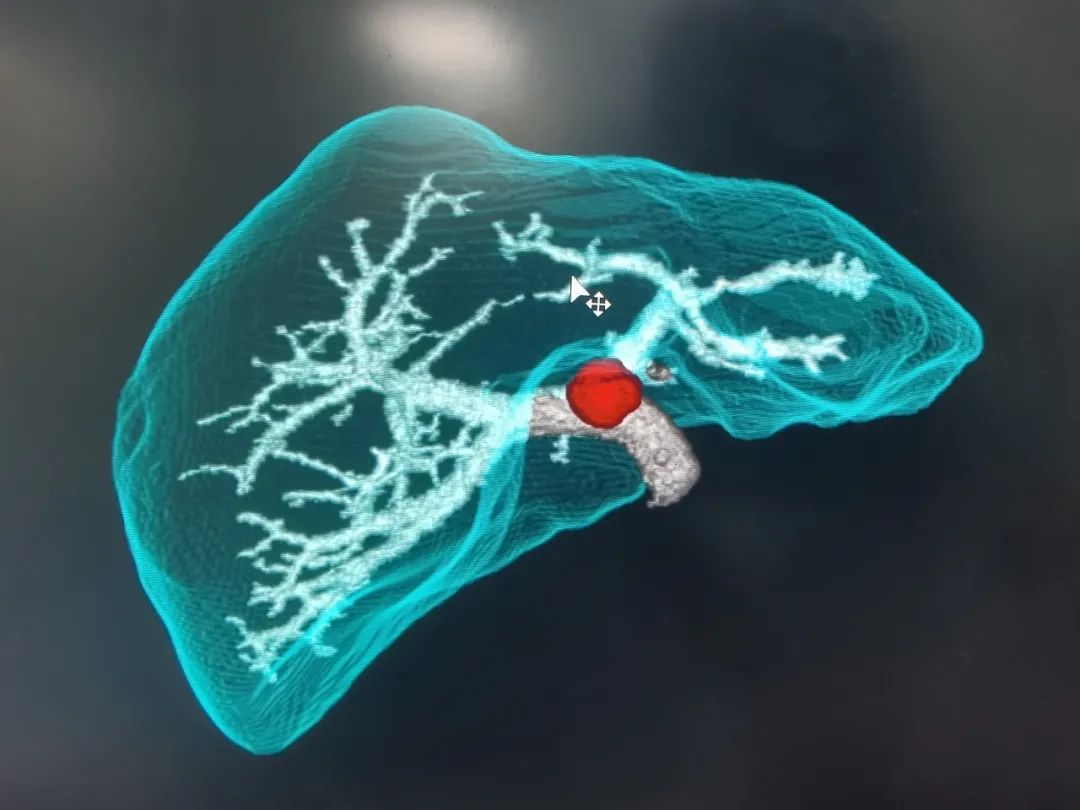

经过详细的体格检查,完善影像和实验室检查后,诊断其为:肝门胆管恶性肿瘤。普外科主任代坤介绍,肝门部胆管癌,就是长在肝门部胆管粘膜上皮的恶性肿瘤,因为位置特殊,起病隐匿,可能与胆管慢性炎症、胆管结石等有关。长期胆管炎会让胆管粘膜反复受损修复,胆管粘膜增生,可能发展成癌;有先天性胆管囊性扩张症、原发性硬化性胆管炎的人群,患癌的几率更高。值得警惕的是,患者早期症状可能不明显,随着肿瘤的生长,胆管被堵住,胆汁排不出去,黄疸会特别突出,出现皮肤、巩膜黄染,患者可能会有右上腹隐痛、胀痛,因为肿瘤影响消化,患者营养吸收不好消耗较大,会有吃不下饭、消瘦、没力气的表现。

基于术前影像,结合肿瘤实际累及程度、解剖变异以及切离极限点,外科团队邀请多科室开展MDT讨论,规划个体化精准手术方案。充分术前准备后,为其行“肝门部胆管癌根治术”。主刀手沉着冷静,仔细探查,精准分离,清扫组织,以雷霆之势完整切除病灶。“清点器械纱布,确认无误,关腹。”手术顺利,经过术后严格管理和精心护理,宗师傅很快康复出院,对东方医院集团广济医院普外科团队精湛的技术赞不绝口。